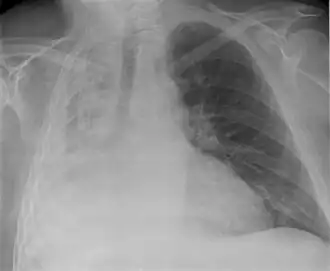

| Raio X de atelectasia do pulmão direito. | |